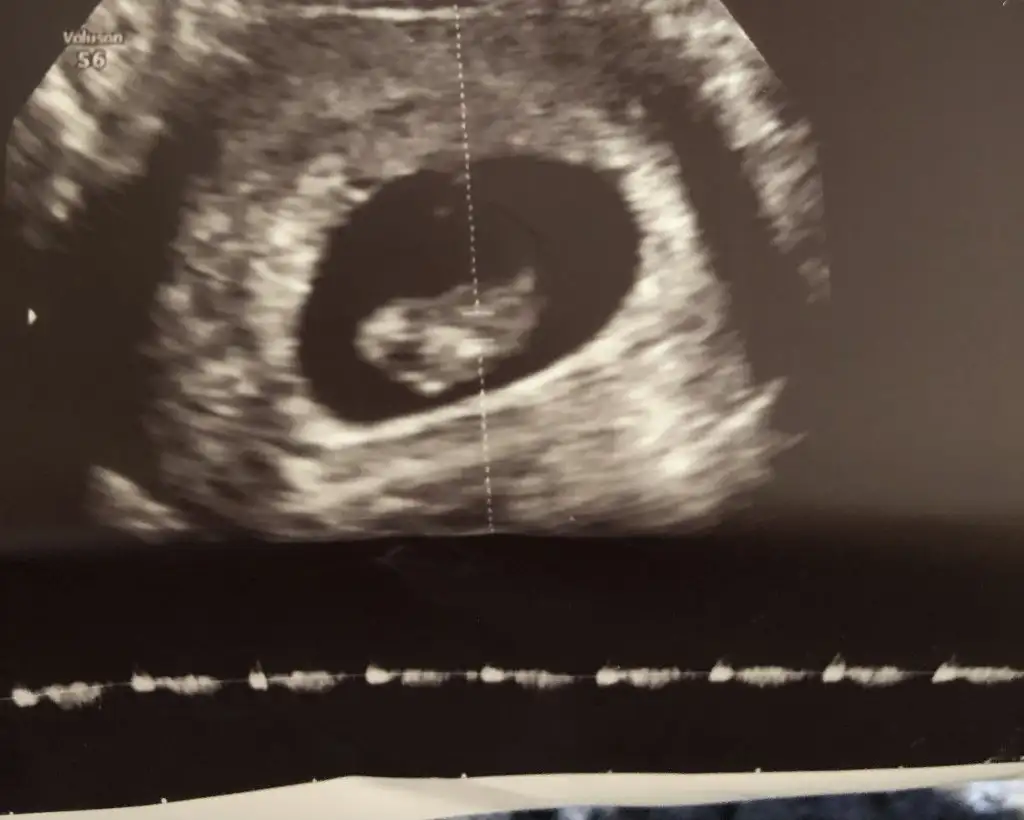

Çok iyi anlıyorum bende aynı durumdayım🤗 ama keseden tahmin nasıl olcak ki doktorlar bile öyle birşey olmadığını söylüyorlar biraz sabretmek lazım ❤️❤️❤️🤱👼🏻👼🏻👼🏻

Evet canim cok haklisin merak iste sabirsizlaniyorum cici cici kiyafetler almak icin aile buyukleride sabirsizlaniyo ilk torun hazirlik yapmak icin❤❤